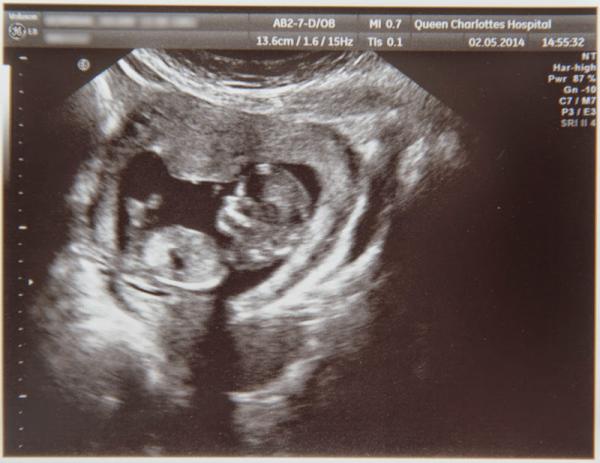

PosyFossilsShoes · 03/05/2014 12:44

Scan photo! It's a bit of a crap picture, I was slightly disappointed - as they charge £4 for them you'd have thought they'd make an effort to get a decent snap, but never mind.

Look at the little nose!